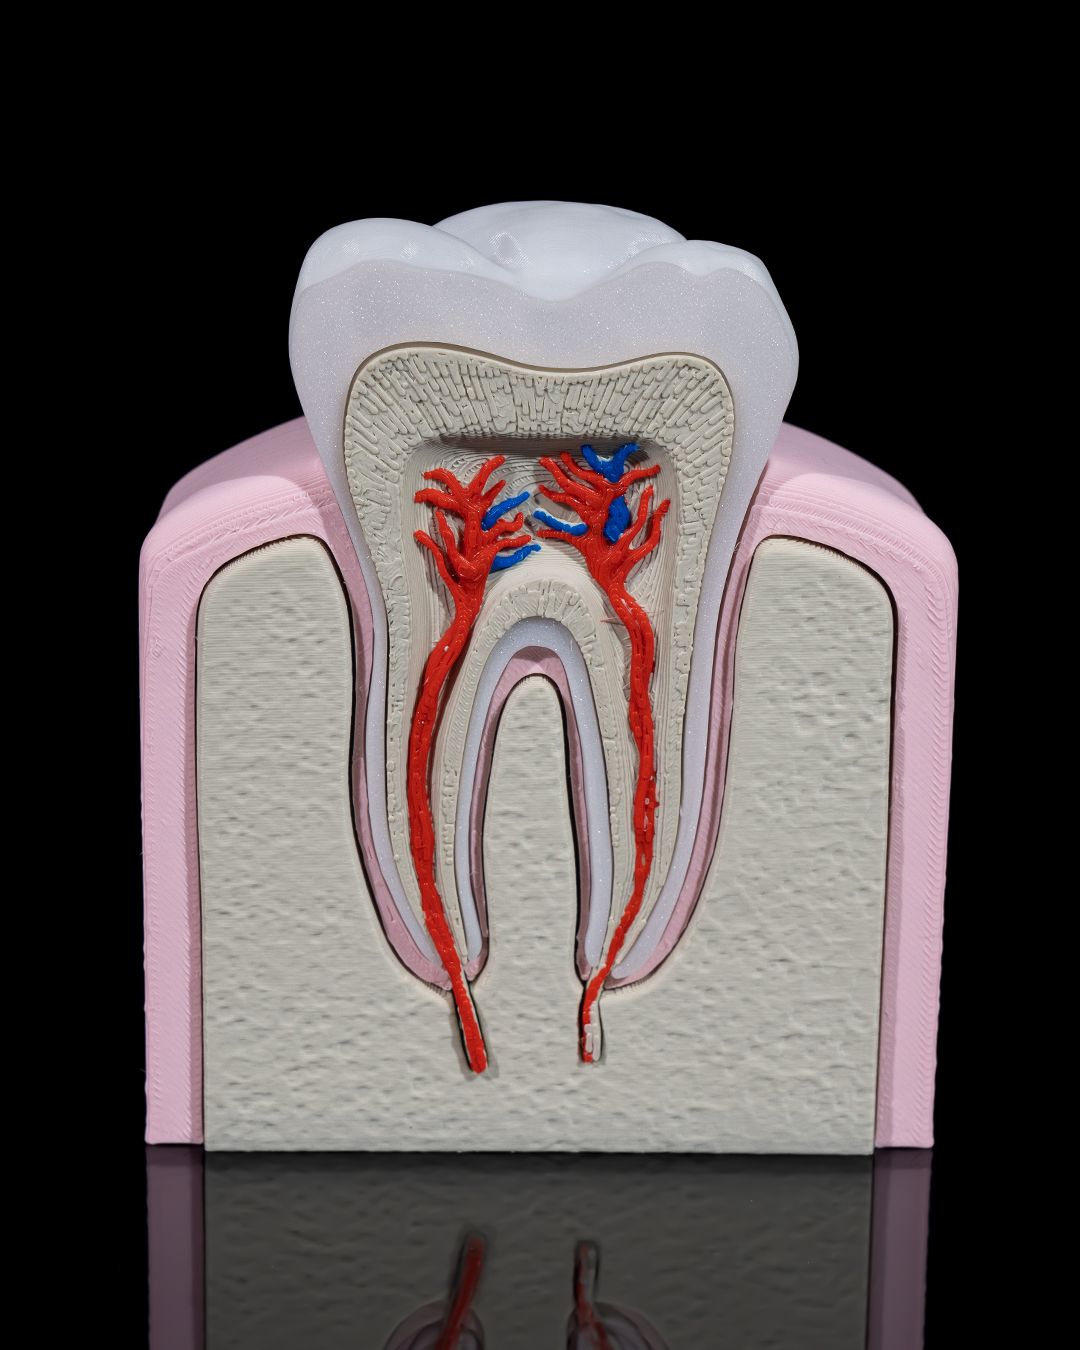

🦷 3D Printed Healthy Premolar Tooth – Precision You Can Smile About

Perfect for dental education, display, or interactive learning, this anatomically accurate premolar model showcases the structure and strength of a healthy adult tooth. It’s a striking blend of science and craftsmanship, ideal for classrooms, clinics, and curious minds.

- True-to-life size and shape for tactile exploration

- Clearly defined cusps, root formation, and enamel contours

- Excellent for explaining oral hygiene, dental anatomy, and procedures